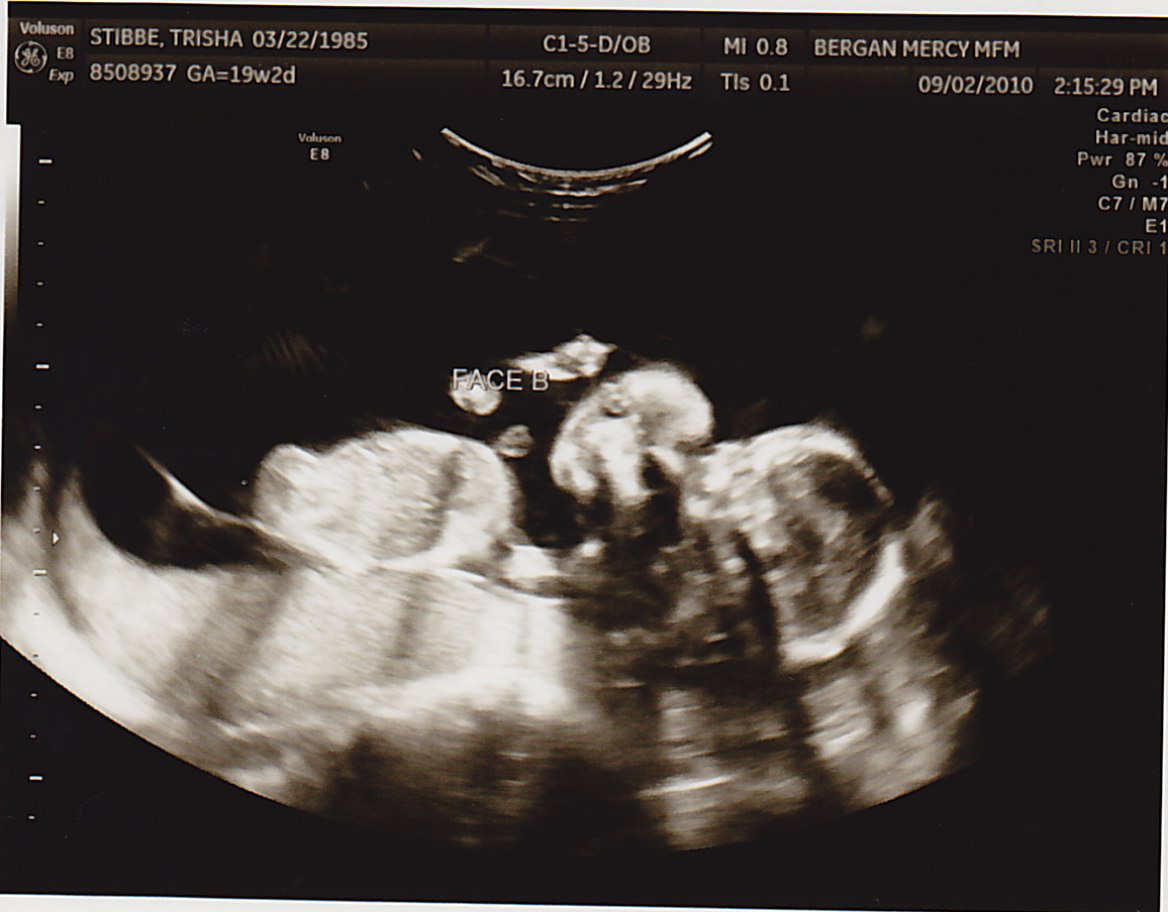

TODAY was a great appointment- we found out Baby B had a lot more fluid around himself!!! That means I didn’t have to have more fluid drained (at least for today). Baby A was 8oz and Baby B was 6oz. This is still good news, because two weeks ago Baby A was 6oz and Baby B was 4oz. As long as they’re both gaining the same amount of weight from here on out, we’re very positive everything will be okay. The difference between them just needs to continue to lessen.